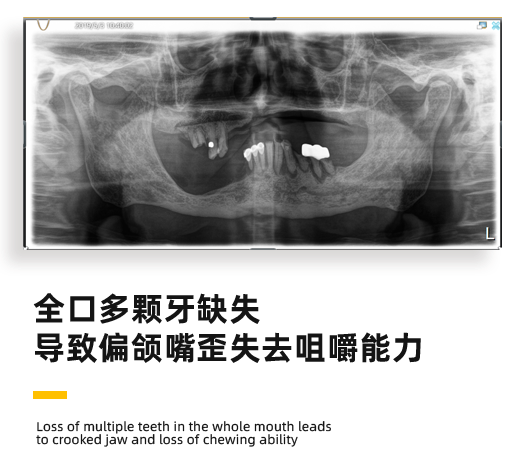

来看诊的时候,恽爷爷全口多颗牙缺失,已经失去了咀嚼的能力,而且因为牙骨缺失,在外观上爷爷的脸已经出现了严重的歪斜。